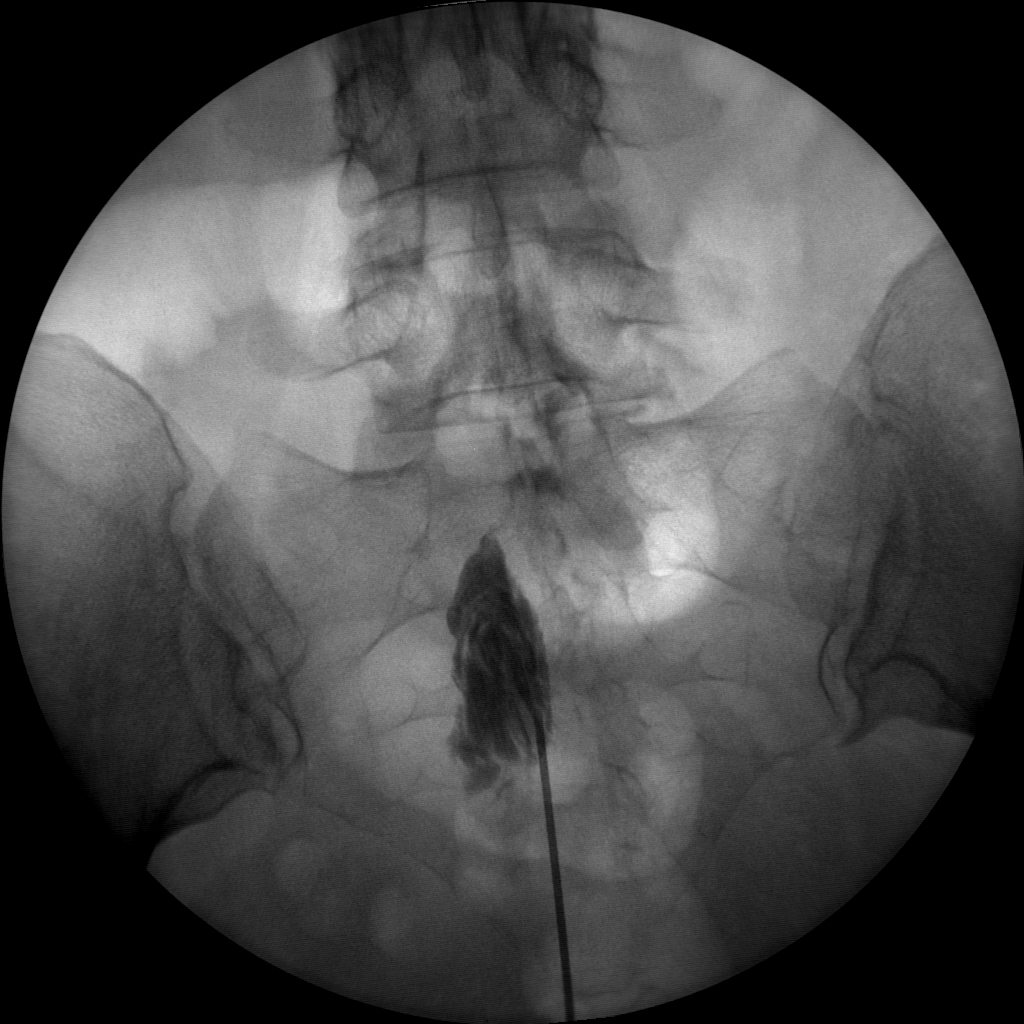

Epidural Injections

The high-resolution 1kx1k images from Skan-C helps pain management professionals visualize the position of the needle in relation to the epidural space, ensuring accurate and effective treatment.